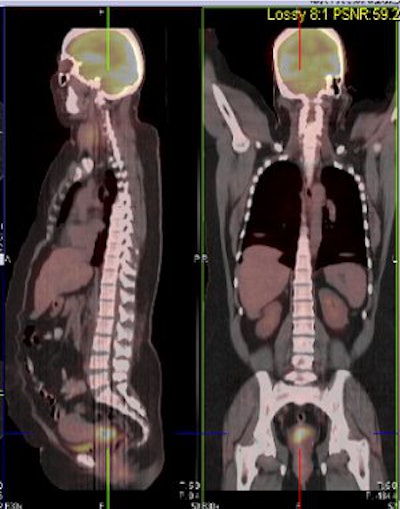

| Above and below, representative images of a 39-year-old patient, currently undergoing treatment, with FIGO stage IB2 squamous cell carcinoma of the cervix. Pretreatment FDG-PET/CT identified an FDG-avid cervical tumor mass plus bilateral iliac and right common iliac metastatic lymphadenopathy. Images courtesy of Dr. Julie Schwarz, Ph.D. |